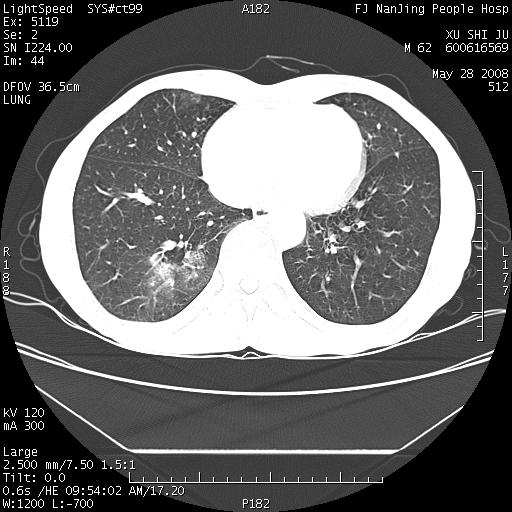

以下是引用杀毒软件在2008-5-28 19:16:00的发言:[br]病灶旁“晕轮征”,考虑肺真菌病

以下是引用qiushi在2008-5-28 20:01:00的发言:[br]空洞周围环状磨玻璃影(日晕征),考虑肺曲霉菌病.

以下是引用yuhongjun在2008-5-29 4:28:00的发言:[br]空洞周围环状磨玻璃影(日晕征),考虑肺曲霉菌病。支持! [br] [br]

以下是引用lrj在2008-5-28 21:10:00的发言:[br]所示应该是正常结构,是对称的,多个层面都有!也不像是内乳动脉或是肿大淋巴结![br]右下肺渗出性病变伴空洞形成,其洞内见一结节,以下诊断都有可能:1 右下肺曲菌感染, 2右下肺结核空洞形成伴曲菌感染!3右下肺结核空洞伴壁内占位形成,虽说后者发生的几率很低 但作为我们应该多考虑一下吧!最重要的结合临床